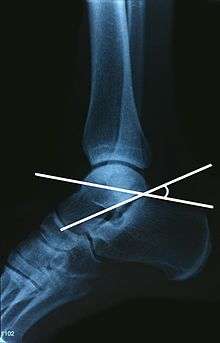

The Angle of Gissane, or "Critical Angle", is the angle formed by the downward and upward slopes of the calcaneal superior surface. On a lateral radiograph, an angle of Gissane of > 130° suggests fracture of the posterior subtalar joint surface. Bohler's angle, or the "Tuber Angle", is another normal anatomic landmark seen in lateral radiographs. It is formed by the intersection of 1) a line from the highest point of the posterior articular facet to the highest point of the posterior tuberosity, and 2) a line from the former to the highest point on the anterior articular facet. An angle < 20° suggests a depression of posterior facet and possible calcaneal fracture.